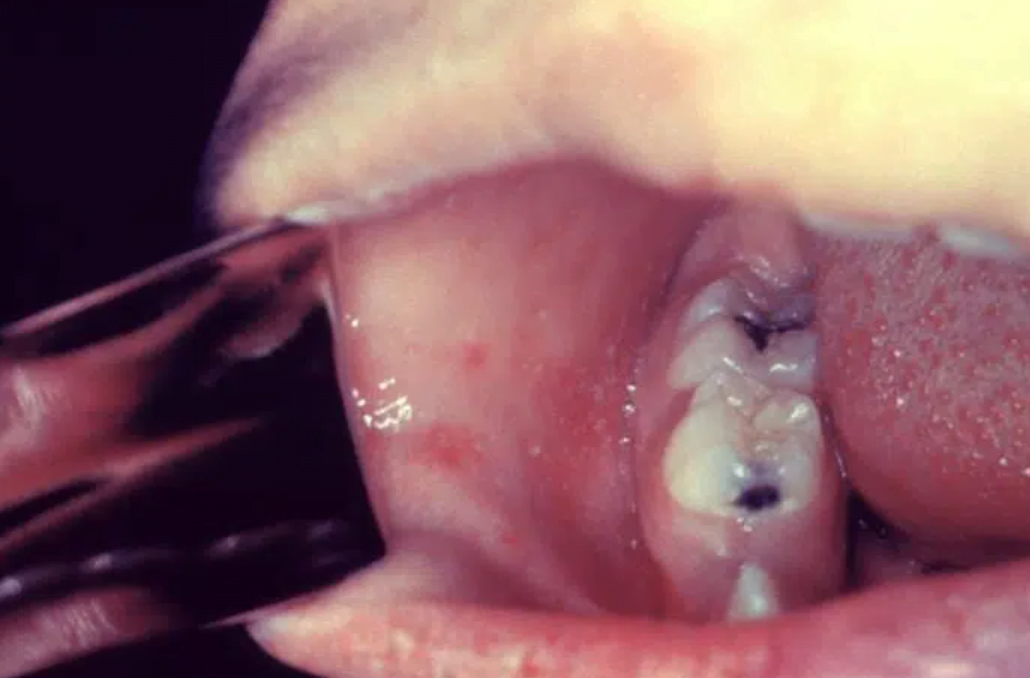

- Koplik spot- lesions on buccal mucosa consisting of pinpoint greys spots surrounded by bright red inflammation.

- MEASLES aka rubeola